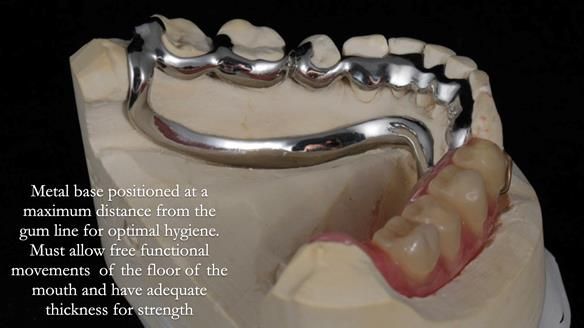

In 2024, my resolution is to revolutionise global teaching and design of partial dentures. I've been inspired by the hygienic Scandinavian approach to RPD design by John Besford, Charlotte Stilwell and Linda Blakely. Since implementing this method, my patients now only need 1.5 reviews after fitting, a significant improvement compared to the 5 reviews required using the the RPI system I was originally taught. It has notably improved the quality of life for my patients. I'm reaching out to you for support in achieving this goal by sharing my newsletters with dentists and educators globally. Together, we can spread this innovative approach worldwide. Your assistance is crucial in making a significant impact.

I explain the hygienic Scandinavian partial design system in this lecture, starting from the 21-minute mark in the video. To watch this segment, please click on the thumbnail below.